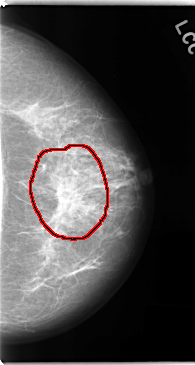

C_0137_1.LEFT_CC

LEFT_CC LINES 4744 PIXELS_PER_LINE 2528 BITS_PER_PIXEL 12 RESOLUTION 50 OVERLAY

FILE: C_0137_1.LEFT_CC.OVERLAY

TOTAL_ABNORMALITIES 1

ABNORMALITY 1

LESION_TYPE MASS SHAPE ARCHITECTURAL_DISTORTION MARGINS SPICULATED

ASSESSMENT 5

SUBTLETY 5

PATHOLOGY MALIGNANT

TOTAL_OUTLINES 1

BOUNDARY